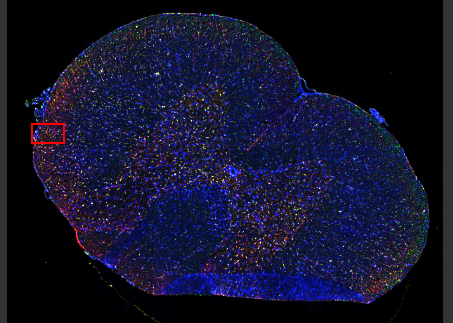

40배율로 획득한 15µm의 쥐 척수 관상 절편의 확장 초점 이미지(EFI).

파란색: X-Cite NOVEM LED를 사용하여 획득한 DAPI. 녹색: NFH(축삭). 노란색: Iba1(미세아교세포). 빨간색: VS-SILA 광학 절단 장치로 획득한 GFAP(성상세포).

샘플은 오스트리아 파라셀서스 의과대학(Paracelsus Medical University), Spinal Cord Injury and Tissue Regeneration Center Salzburg의 Institute of Experimental Neuroregeneration에서 제공했습니다.